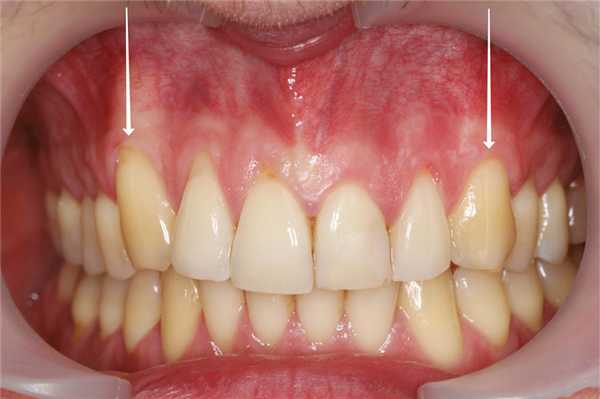

В исследование были включены 25 пациентов с диагнозом локальной рецессии, с клинической картиной, при которой отмечалась рецессия только у одного из идентичных зубов (рис. 1). Рис. 1. Исследование проводили у каждого пациента в области идентичных зубов. В данном случае: зуб 1.3 с рецессией, 2.3 — без рецессии. Исследовали 30 зубов, имеющих рецессию от 1,0 до 4,8 мм. Контрольная группа включала в себя 30 идентичных зубов с противоположной стороны, не имеющих рецессии (6 зубов имели минимальную потерю прикрепления — до 0,5 мм). Возраст пациентов составлял от 21 года до 36 лет, среди них было 13 женщин и 12 мужчин.

В проведенной работе высота КД в области исследуемой группы зубов составляла 1,58 [0,9; 1,9] мм; в контрольной группе она составляла 3 [2; 3,4] мм (см. рис. 3) (p<0,05); выявлена также статистически достоверная корреляционная зависимость между высотой КД и величиной рецессии — 0,64 (p <0,0001). Если учесть, что мукогингивальная линия генетически детерминирована и относительно стабильна, следовательно, зона КД уменьшается из-за апикального смещения десневого края, т. е. в результате рецессии (см. рис. 7, 8). Рис. 7. Измерение высоты КД; зуб 1.3 (слева): клиническая рецессия составляет 1,6 мм, высота КД — 1,6 мм; зуб 2.3 (справа) без рецессии, высота КД — 3.0 мм. Рис. 8. Представлен вариант визуального сопоставления клинических данных и данных КЛКТ зубов 1.3 (исследуемая группа, слева) и 2.3 (контрольная группа, справа). Таким образом, на основании нашей ретроспективной оценки можно предположить, что достаточная высота КД при ее толщине <1 мм не обеспечила полной стабильности десневого края и под воздействием дополнительных факторов привела к рецессии. При этом надо учитывать, что в большинстве исследуемых случаев имело место низкое положение альвеолярного гребня.